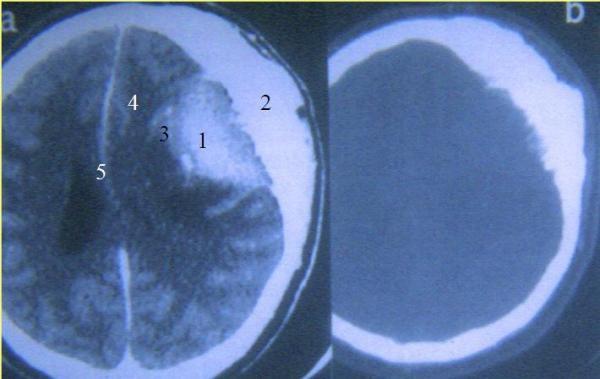

في بادئ الأمر عزا المختصون هذه الحالة الفريدة إلى "اضطراب سلوكي"، ليتبين لاحقا وبعد فحوصات متواصلة أن السر الضحك الذي يبدو من غير سبب يكمن في ورم وراثي حميد في دماغ الطفلة، يضغط على أجزاء معينة في المخ مما يؤدي إلى الضحك.

بعد التحقق من السبب خضعت الطفة لعملية جراحية تعافت منها بشكل تام، واستعادت قدرتها على الضحك بشكل طبيعي كغيرها.